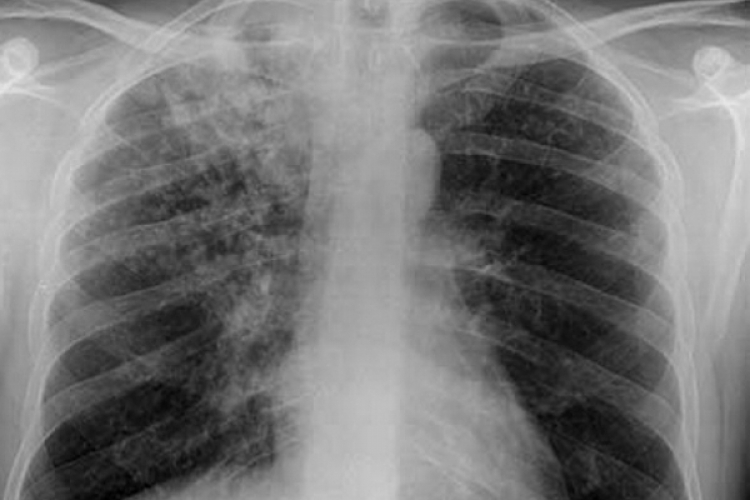

Власти намерены к 2025 году снизить заболеваемость туберкулезом на 50%, а смертность от этого заболевания – на 75%, по сравнению с 2015 годом. Власти также хотят повысить уровень выздоровления среди больных туберкулезом и улучшить доступ к диагностике и лечению для всех граждан. Эти цели предусмотрены в Национальной программе реагирования на туберкулез в 2022-2025 годы, утвержденной правительством, передает IPN.